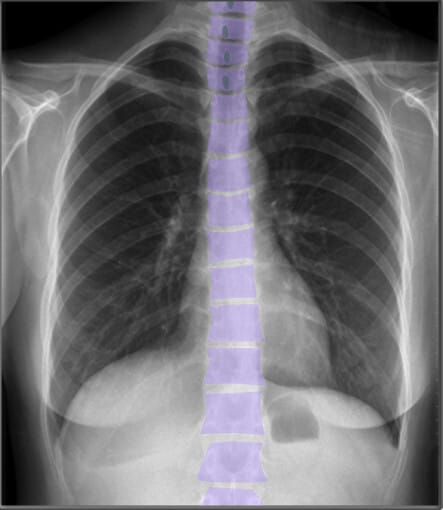

Bones (PA view)

흉부 X-ray에서는 쇄골(clavicle), 흉골(sternum), 견갑골(scapula), 척추(vertebral bodies) 등의 뼈 구조가 보이며, 정상적인 정렬을 확인하는 것이 중요합니다.

| 척추체 (Vertebral Bodies) |

| ✅ 흉추(Thoracic vertebrae)의 척추체는 X-ray에서 선명하게 보여야 하며, 정상적으로 정렬되어 있어야 합니다. 압박 골절이나 변형이 있는지 평가하는 것이 중요합니다. |

위 사진에서 남색으로 표시된 부분은 Spinous Process 입니다.